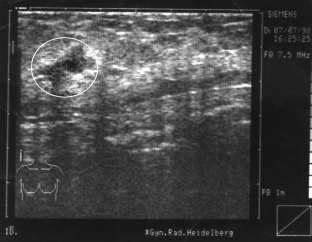

Innerhalb von 2 Tagen wächst dieser große Knoten in der linken Brust der Klientin. Der Prof. will die Brust abnehmen. Die Klientin aber nutzt die kurze Zeit bis zum OP-Termin zur Selbstheilung und läßt sich von Brigitte mit 6 Synergetik Therapie Sitzungen helfen, den Hintergrund selbst aufzulösen. Dazu mußte es einen konkreten Auslöser mit dem Thema „Kind“ geben, der so schnell arbeitete und den Knoten produzierte. Dieser war leicht zu finden und der wirkende Kontext in der Innenwelt wurde verändert. Der Prof. staunte nicht schlecht, als er den Knoten per Ultraschallbild nicht mehr finden konnte. ... Er interessierte sich für die Synergetik Therapie und lädt Brigitte Schiechel zur Zusammenarbeit ein.

Nachher: